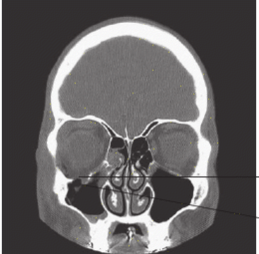

Name the fracture shown in the CT image below and the complication typically associated with this injury.

What is a blow-out orbital fracture and ocular muscle entrapment?